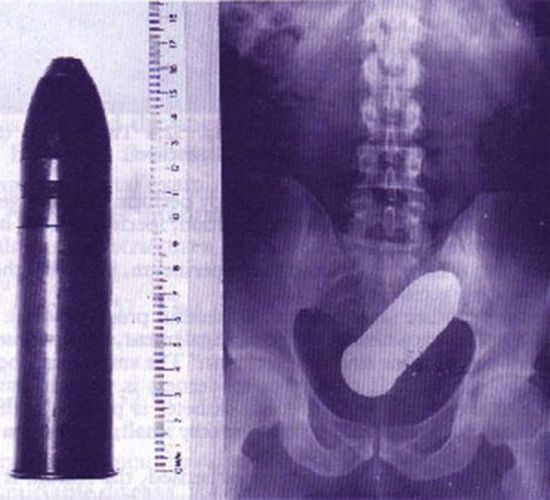

Quando o prazer vira um caso de emergência médica. Pessoas que se excederam e foram parar na emergência em função de objetos bizarros introduzidos no ânus. Confira.

Bala de Revólver